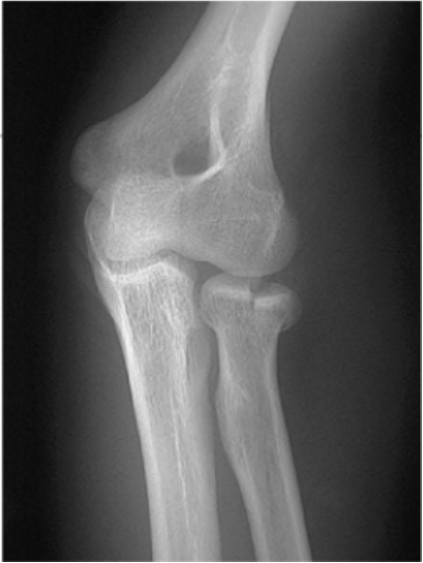

Que fractura se presenta en esta imagen

Colles